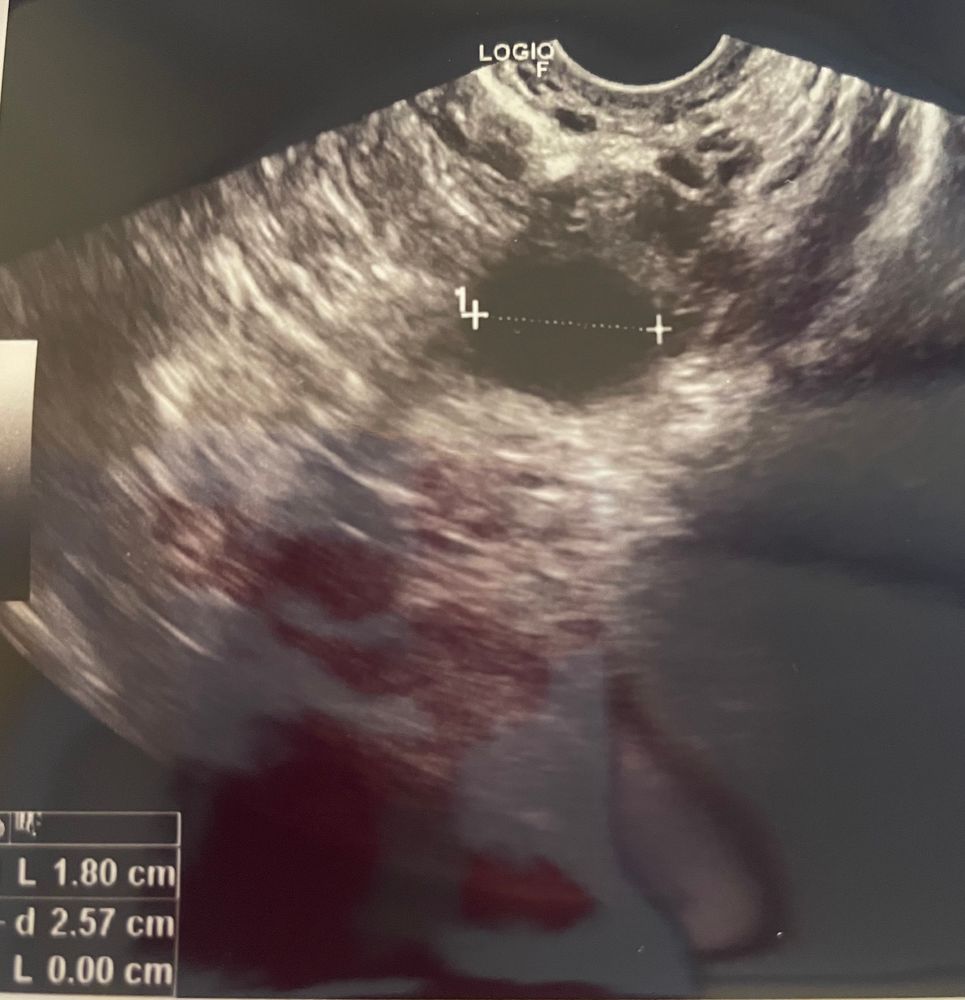

18 дц 🐣2 дпо 💫3 дпу ☄️ яичник редко ощущаю, хочу спать , голова даже кружится в транспорте, грудь тоже немного , но это от овитреля . Сбегала на узи. В ля жт 21 мм с хорошим кровотоком, эндик 13,3.. немного жидкости..все хорошо🤔 врач восхищалась, только вот где беременность не понятно..